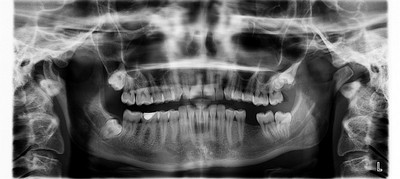

임플란트는 단순한 치과 치료를 넘어, 오랜 기간 내 치아를 대신할 소중한 구조물이 됩니다.

한 번 시술하면 수십 년 이상 사용할 수 있는 만큼 처음 선택이 매우 중요한데요.

임플란트는 대부분 티타늄 합금으로 제작되며, 시술이 정확하고 꾸준히 관리하면 수십 년 이상 사용도 가능합니다. 무엇보다 시술자의 경험과 정확성이 최종 결과를 결정짓는 중요한 요소입니다.